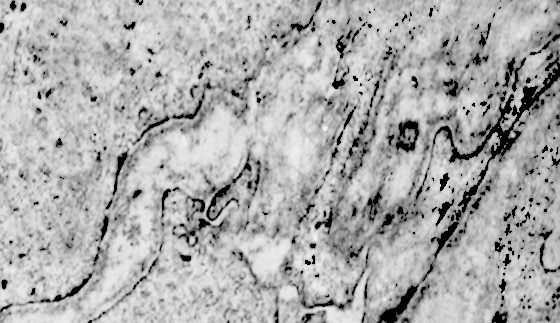

Nel citosol si repertano vescicole di piccole dimensioni delimitate da una membrana di contorno a mono strato. Il loro lume è occupato da materiale amorfo e da corti filamenti distribuiti in modo disordinato.

Queste vescicole sono distribuite in modo irregolare, anzi casuale e si ritrovano ad essere isolate o riunite in piccoli aggregati formando un’immagine definita corpi multivescicolari.

Frequentemente questi focolai si ritrovano commisti ad altri aventi i caratteri della macroautofagia e sono in parte da questi mascherati. A parte questi particolari reperti,il citosol è occupato da numerosi mitocondri di piccole dimensioni e di forma rotondeggiante e di aspetto compatto,da ergastoplasma rugoso e da quote ben rappresentate di reticolo endoplasmico e di strutture lisosomiali.